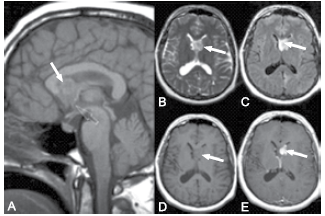

Criança de 5 anos com deficiência intelectual, crises convulsivas e, no exame físico, apresentando placas em região de dorso da região lombossacra conforme demonstradas na figura 1. Durante investigação, foi realizada ressonância de encéfalo que apresentou a alteração demonstrada com a seta branca na figura 2.

Figura 1

Bertolucci, Paulo Henrique Ferreira, et al. Neurologia: diagnóstico e tratamento. (2016).

Figura 2